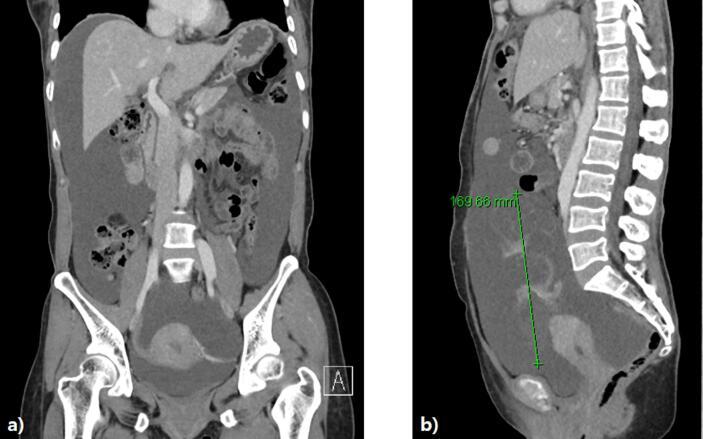

Concurrent metastatic ovarian adenocarcinoma of endocervical adenocarcinoma in situ: A case report emphasizing pathologic diagnostic key points and clinical progress.

https://cdn.ncbi.nlm.nih.gov/pmc/blobs/6c51/8080020/e841a8d3532c/gr1.jpg